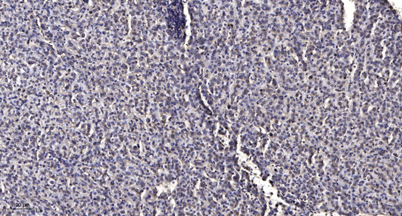

IF

IHC

Recomended Dilution Western Blot: 1/500 - 1/2000. Immunohistochemistry: 1/100 - 1/300. ELISA: 1/20000. Not yet tested in other applications.